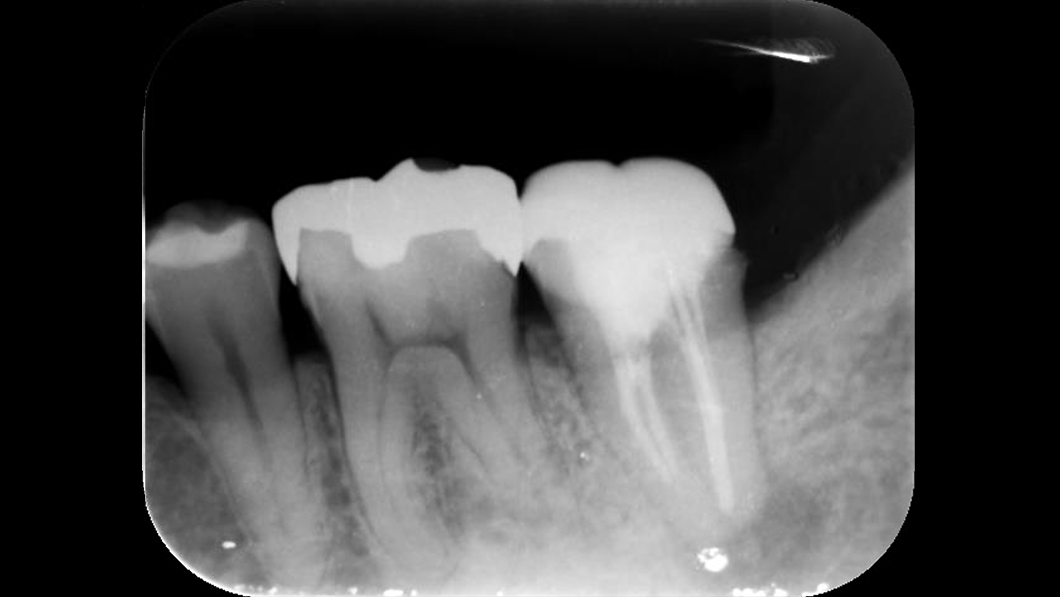

意図的再植

- 補綴物除去後歯牙を一度抜歯。口腔外で根切および根管形成を行い逆根管充填後口腔内へ戻し固定。

動揺落ち着いたのを確認後CAD/CAM冠にて補綴

- 術中:抜歯時に歯根破折の可能性

術後:歯根吸収(置換性吸収)、付着の部分的非獲得(部分的な深いポケットの形成)